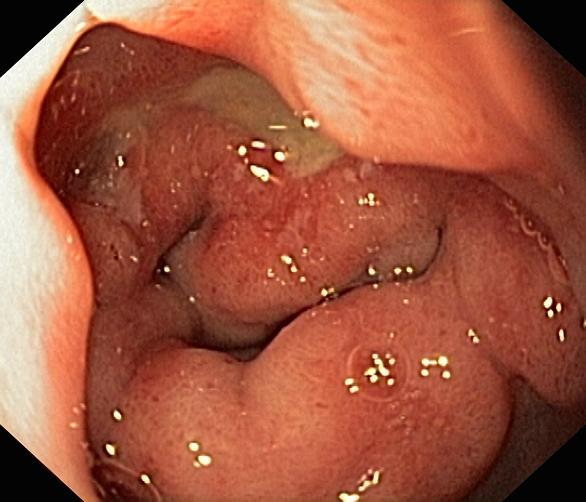

Wrzód trawienny